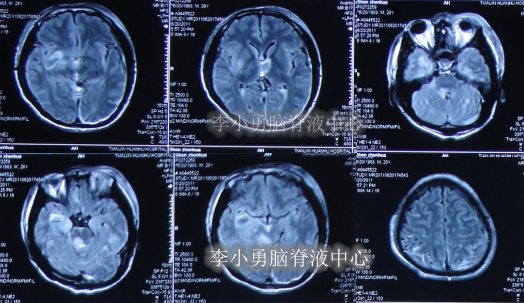

患者于2011年6月20日,因意外车祸致全身多器官损伤昏迷,当天住入天津著名的三甲脑科医院,检查明确颅脑外伤、肺挫伤、骨盆骨折(片子丢失),头部MRI和CT提示颅骨骨折,脑干弥漫性轴索损伤,颅内有出血,水肿(图-1、图-2)。

图-1:2011年6月20日头部MRI

图-2:2011年6月20日头部CT